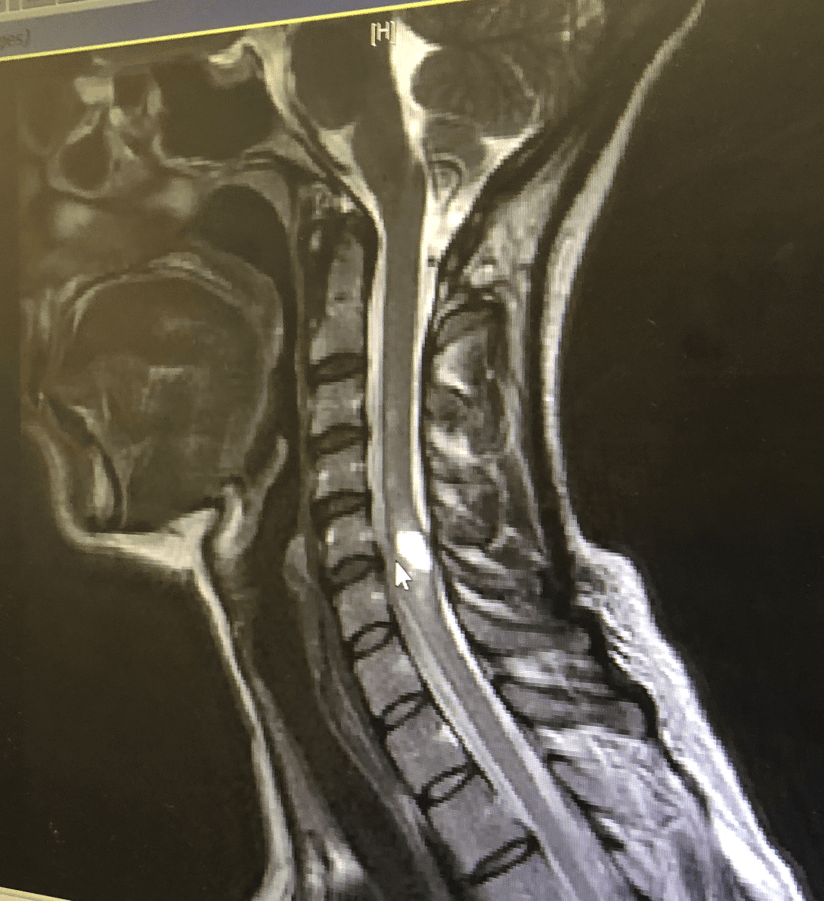

Shortly after I finished nursing our youngest baby, I began having seizures that lead to the discovery of 23 tumors in my neurological system and a diagnosis of Neurofibromatosis II (NF2).

After having 2 craniotomies to remove meningiomas, we learned why the symptoms showed themselves so suddenly; the same hormones that created those babies had actually caused my tumors to grow as well.